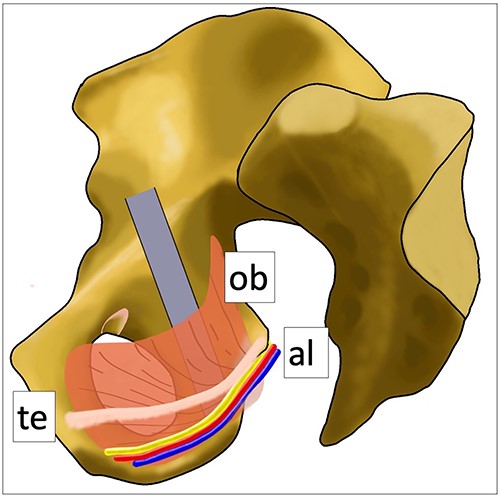

In this technique, there are some tricks and traps. First, a sharp retractor should not be inserted into the obturator muscle near the ischial tuberosity and the lower end of the quadrilateral space. Alcock’s canal, including the pudendal vessels and nerve, is folded inside the wall of the obturator muscle [13, 14], and attention must be paid not to injure them (Fig. 8). The pudendal nerve, which has three branches (inferior rectal nerve, perineal nerve, dorsal nerve of the penis in males, and dorsal nerve of the clitoris in females), is associated with urinary and sexual function [15]. Second, rough retraction of obturator nerve should be avoided. Third, as the sciatic nerve is close to the posterior wall, overdrilling must be avoided.

Anatomical schematic diagram. This schematic diagram shows the anatomical relationships of the internal obturator muscle, Alcock’s canal and the tendinous arch of the levator ani muscle. Ob: internal obturator muscle, al: Alcock’s canal (pudendal vessels and nerve), te: tendinous arch of the levator ani muscle.